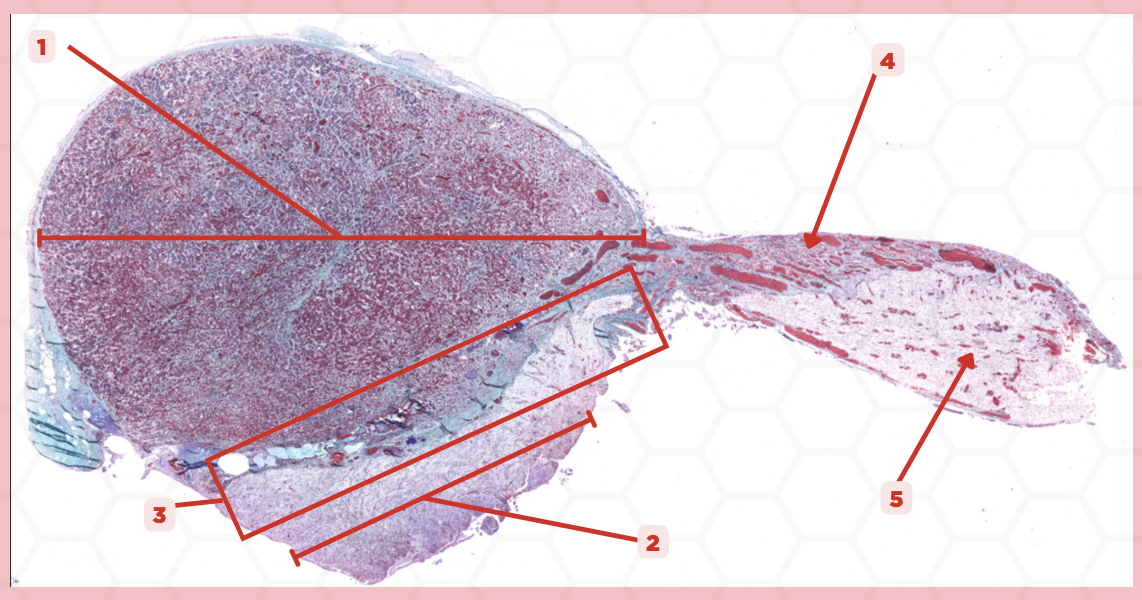

Pituitary

Identify the specimen.

Anterior Lobe

Identify the structure labeled as 1.

Posterior Lobe

Identify the structure labeled as 2.

Intermediate Lobe

Identify the structure labeled as 3.

Pars Tuberalis

Identify the structure labeled as 4.

Pituitary Stalk

Identify the structure labeled as 5.